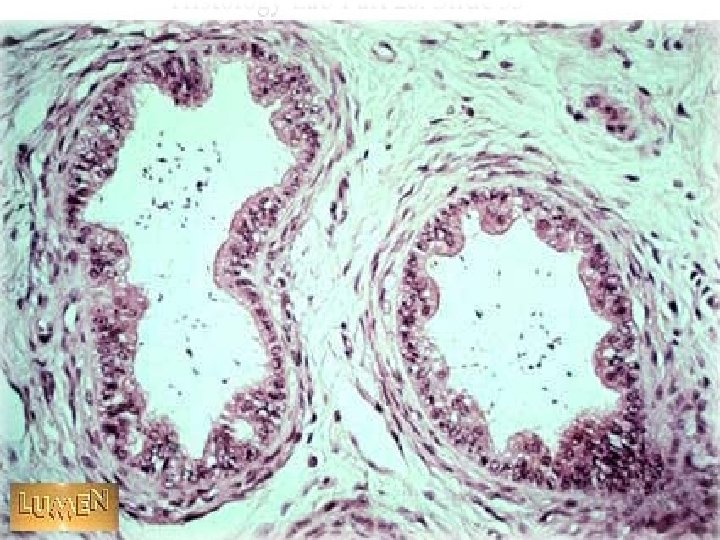

efferent ductules

2. dutus epididymis l 4 -6 m,highly convoluted l pseudostratified ciliated columnar Epi. =principal C + basal C l lumen is regular,filled with sperm & secretions l the proximal , efferent ductules; the distal, ductus deferens.

dutus epididymis

Epi. dutus epididymis